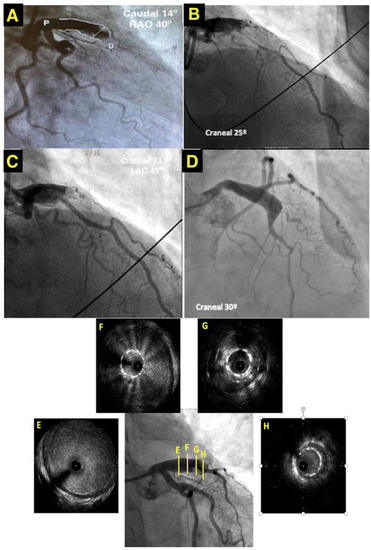

The patient underwent an emergent coronary angiography due to this anterior ST-segment-elevation myocardial infarction. The coronary angiography revealed CAA, extending from the left main stem to the proximal segment of the anterior descendent artery (LAD) and a thrombotic occlusion (TIMI 1 flow) of its distal segment (Figure 1A/Video S1). Two guidewires were crossed to the distal segment of the LAD and the first diagonal. After percutaneous thrombus aspiration, the flow of the LAD was not restored. A perfusion of a glycoprotein IIb/IIIa inhibitor class (eptifibatide) was initiated during the procedure. A microcatheter was then crossed to the distal segment of the LAD and contrast was infused from the microcatheter and support catheter simultaneously in order to check the distal vessel’s diameter and to confirm the extension of the occlusion (Figure 1B/Video S1). Then, a 2.75 × 28 mm drug-eluted stent was implanted covering the occlusion, with its size adjusted to the distal segment of the aneurysm (Figure 1C).

An intravascular ultrasound (IVUS) was performed thereafter, showing the stent “floating” in the aneurysm covered by thrombus (Figure 1E–H). A post-dilatation with a 3 non-compliant balloon in the distal segment of the stent improved the distal stent apposition and a post-dilatation with a 5 mm non-compliant balloon in the proximal segment resulted in a “funnel”-like shape (Figure 1D/Video S2). The LAD regained normal coronary flow (TIMI III).

Figure 1. (A) CY showing a CAA with a maximum diameter of 8.49 mm (white double arrow). (B) CY displaying simultaneous contrast infusion from the microcatheter and support catheter. (C) CY showing aneurysm after stent implantation. (D) CY displaying the “funnel” shape of the distal segment of the aneurysm after the post-dilatation. (EH) Coronary IVUS showing the stent apposition along the CAA in the ADA showing the stent “floating” in the aneurysm surrounded by thrombus. RAO: Right anterior oblique. LAO: Left anterior oblique.